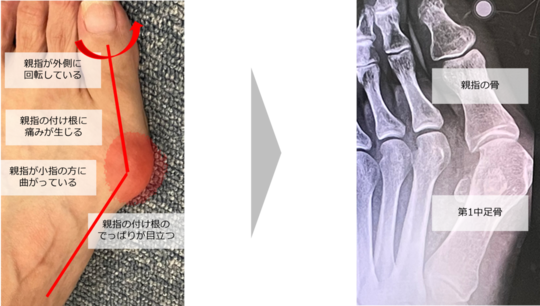

足の親指が外側に曲がって歩行時の痛みを伴う【外反母趾】

足の親指が外側(小指側)に曲がってしまう病気です。

親指のつけ根からの変形【出っぱり】が顕著なため、見分けがつきやすい病気といえるでしょう。

指の付け根から変形に加えて、腫れやズキズキした痛みが現れます。悪化すると、靴が履けなくなったり歩けなくなったりするケースも少なくありません。

親指の関節は通常、人差し指のほうに沿って曲がっていますが、この角度が20度以上のものを外反母趾とすることが一般的です。

外反母趾の角度が

20~30度➡軽度

30~40度➡中等度

4

0度以上➡重度で手術の対象となります。

症状が悪化すると、親指の腹が小指側を向くようにねじれ、人差し指の下にもぐり込むような形状になる場合もあります。